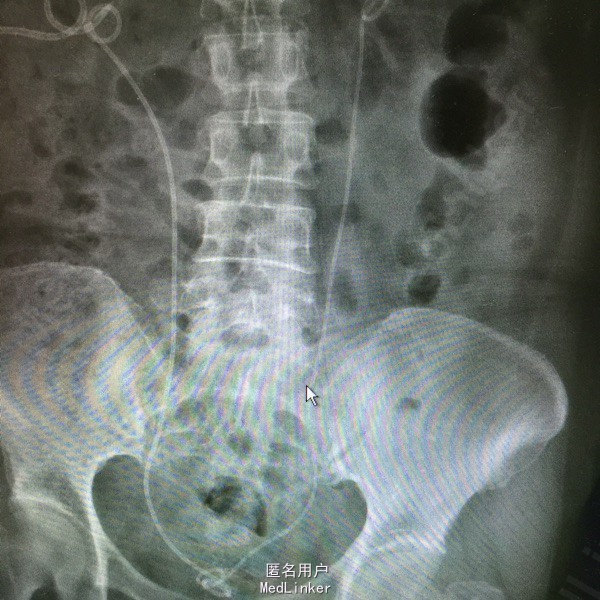

女患60岁 主诉:肾积水1个月 病史:1个月前,患者出现肾造瘘术后堵塞,入我院换管 既往八年宫颈癌前子宫切除,六年前因放疗术后输尿管下段狭窄,右侧行再植术,左侧行双J管植入术后,拔管后1年,发现肾功能不全,于我院行右侧置管术,左侧双J管植入术

查体:肾造瘘管堵塞 辅查:右肾造瘘 左肾双J管植入术后

介入下行右侧肾造瘘更换术,顺输尿管向膀胱留置导丝,输尿管镜下取出导丝,沿造瘘口顺行置入双J管一枚